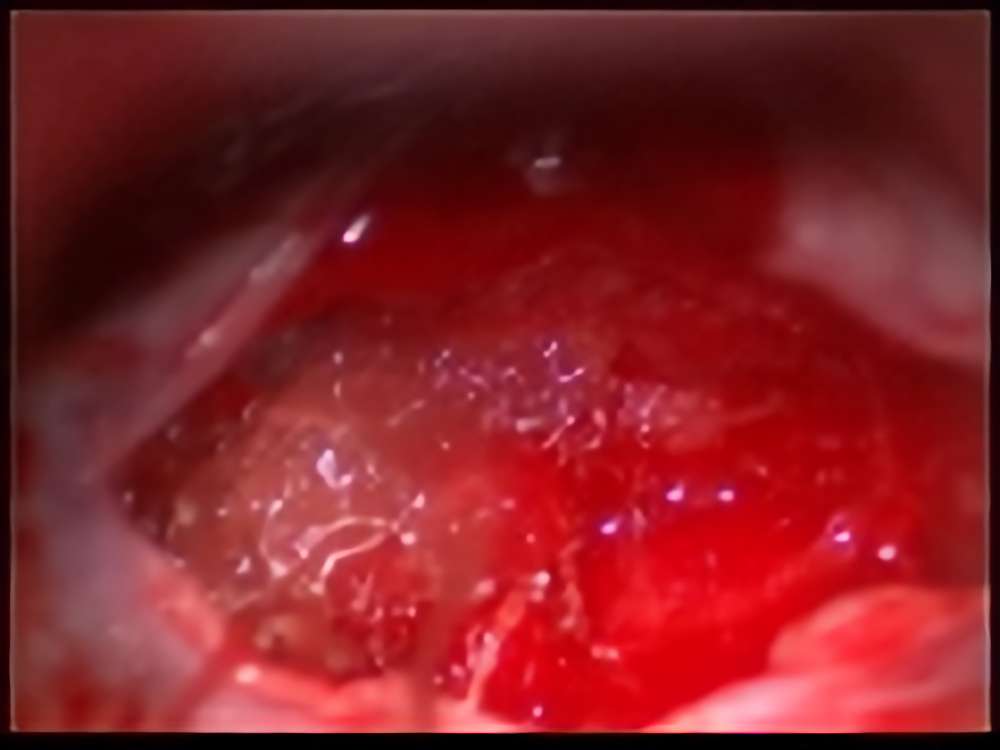

30代

左海綿状血管腫

No.’15_163 手術前1

No.’15_163 摘出 前

No.’15_163 摘出 後